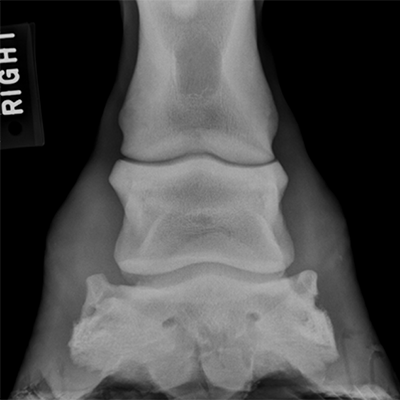

I looked up an image of a normal hoof x-ray:

Now here is Griffy’s – see if you can spot the difference, it’s subtle: